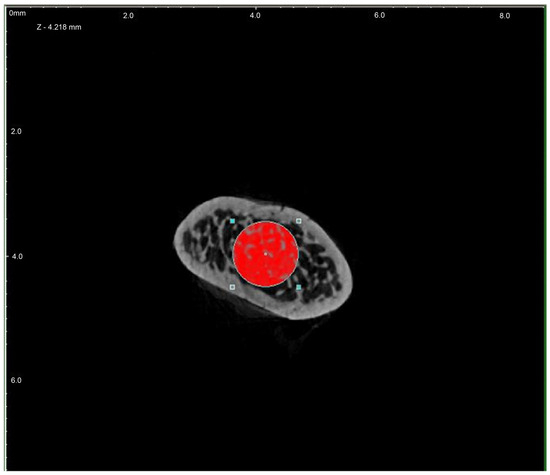

Figure 2.

Region of interest (ROI) chosen for investigation—cross-section (red).